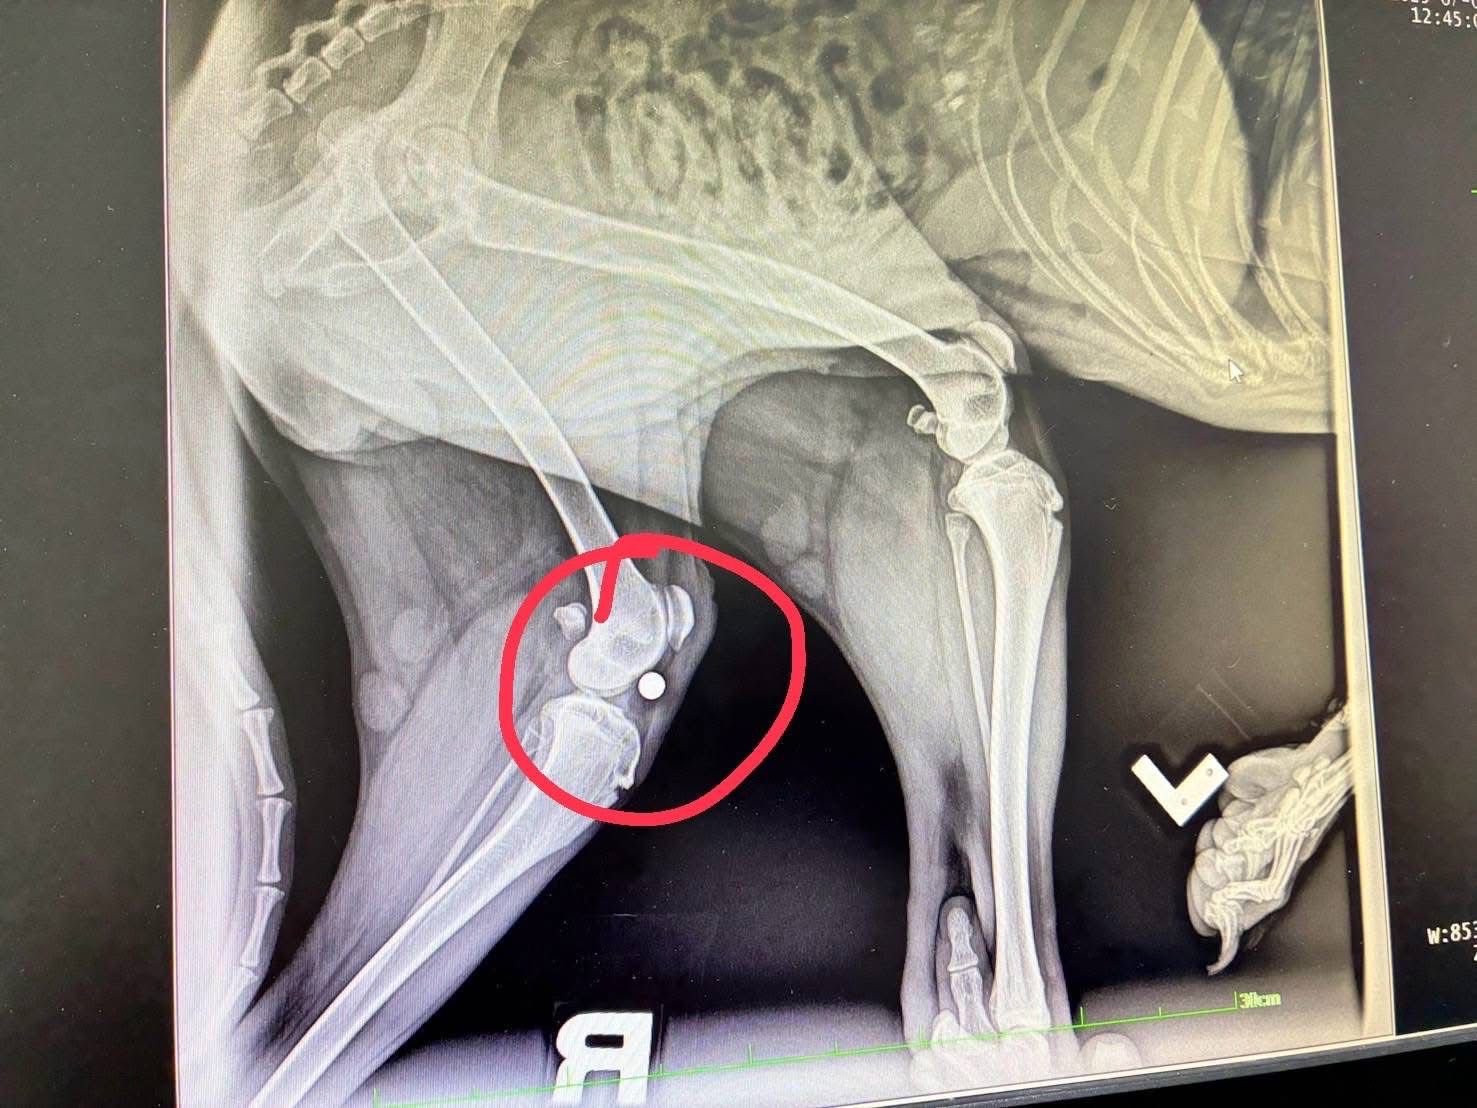

เมื่อวันที่ 1 กรกฎาคม 2568 พระครูสังฆรักษ์วีรวัฒน์ วีรวฑฺฒโน (พระครูอ๊อด) วัดเจดีย์หลวงวรวิหาร จังหวัดเชียงใหม่ เปิดเผยว่า ได้รับรายงานจากมูลนิธิ ดิอาร์ค ในพระราชูปถัมภ์ ซึ่งรับดูแลสุนัขพันธุ์ร็อตไวเลอร์จำนวน 4 ตัวที่ถูกนำไปทิ้งไว้กลางป่าในสภาพหิวโซและมีอาการบาดเจ็บหลายแห่ง โดยหนึ่งในสี่ตัวนั้นอยู่ในอาการบาดเจ็บสาหัส ล่าสุดเจ้าหน้าที่เไดมูลนิธิฯได้ทำการตรวจพบโลหะคล้ายกระสุนฝังอยู่ในร่างกายและอยู่ระหว่างดำเนินการผ่าตัดนำออกอย่างเร่งด่วน